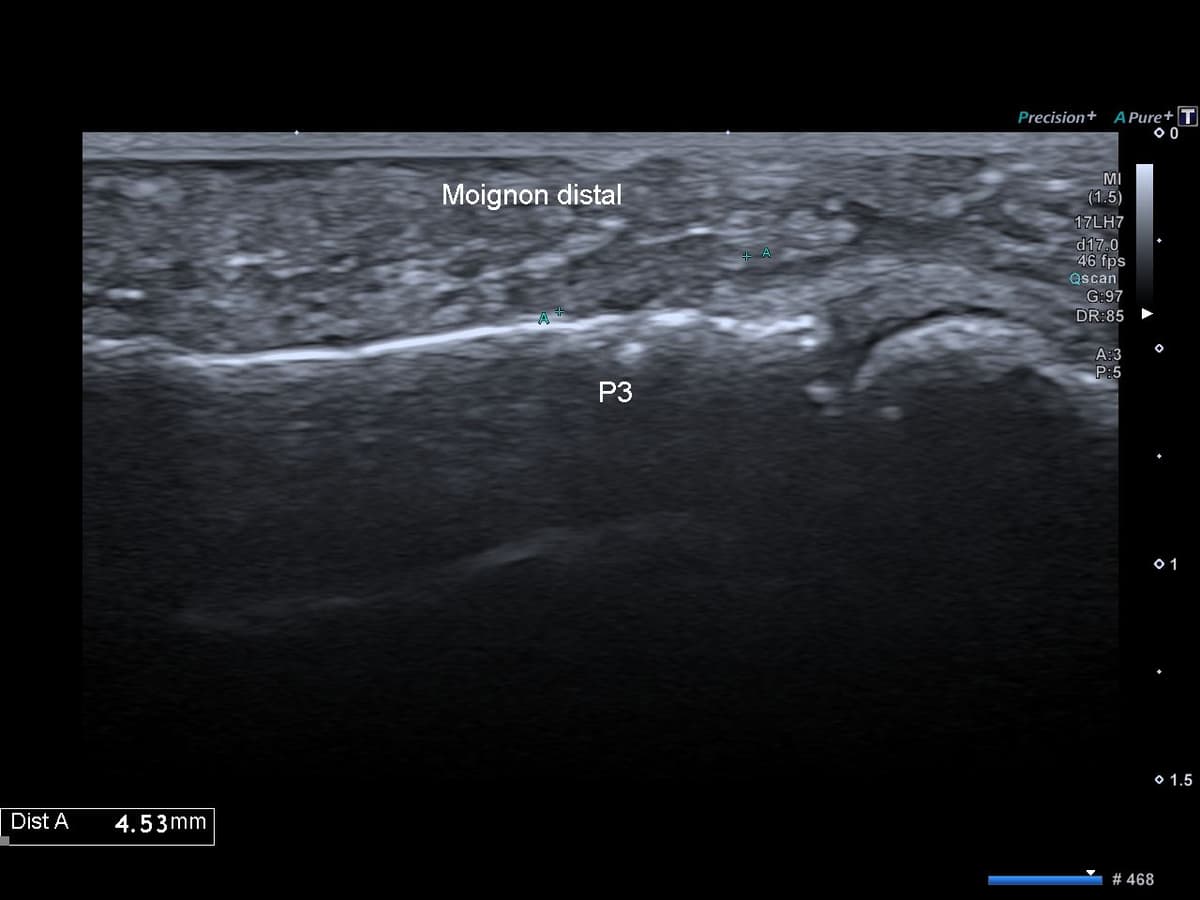

Rupture complète de l'insertion distale du tendon fléchisseur profond des doigts

US